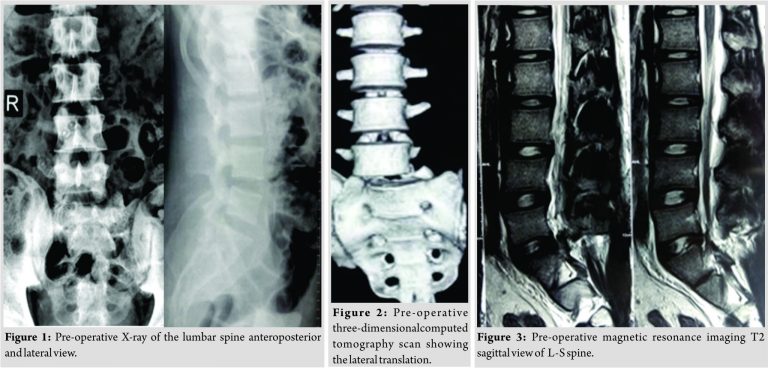

A 22-year young male sustained motor vehicle accident while driving a truck on a highway. Although not sustaining any life-threatening serious injuries, he injured his back and complained of severe debilitating back pain on presentation along with difficulty in moving his left lower limb with difficulty in micturition. On further examination and investigation, he was found to have traumatic spinal instability with traumatic lateral translation of spine along with retrolisthesis at L5-S1 level. On examination, he had a left foot drop with ankle areflexia and severe tenderness at lumbosacral spine. X-ray revealed the right lateral translation at L5 over S1(Fig.1). Computed tomography scan showed lateral translation of spine along with retrolisthesis on sagittal view, with the left facet joint fracture of L5-S1(Fig. 2).

Magnetic resonance imaging (MRI) showed left L5-S1 root compression at foraminal level without signal changes at any other level (Fig. 3 and 4). He was operated on for reduction of translation, decompression, and stabilization. Biplanar instability was reduced with fixation using pedicular screws. L5 laminectomy was performed to decompress the roots, but both L5 and S1 roots were avulsed. Fixation was spanned from L4 to ilium. L5-S1transforaminal lumbar interbody fusion was performed using interbody cage and autologous iliac crest bone graft(Fig. 5).